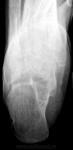

+1. Для опыта по-рекомендовал бы сделать аксиальный снимок и томограммы.

P.S. При интраоссальной липоме характерны центральные обызвествления

Глубокоуважаемый Валентин Львович! Ничего такого про злокачественность я не говорила. Я спросила: почему это интраоссальной липомы "хватит" для диф. ряда? Тем более, что здесь есть вздутие, нет обызвествлений, т.е. не самая характерная картина для интраоссальной липомы

На самом деле, я бы в заключение вынесла "кисту" и рекомендовала МРТ